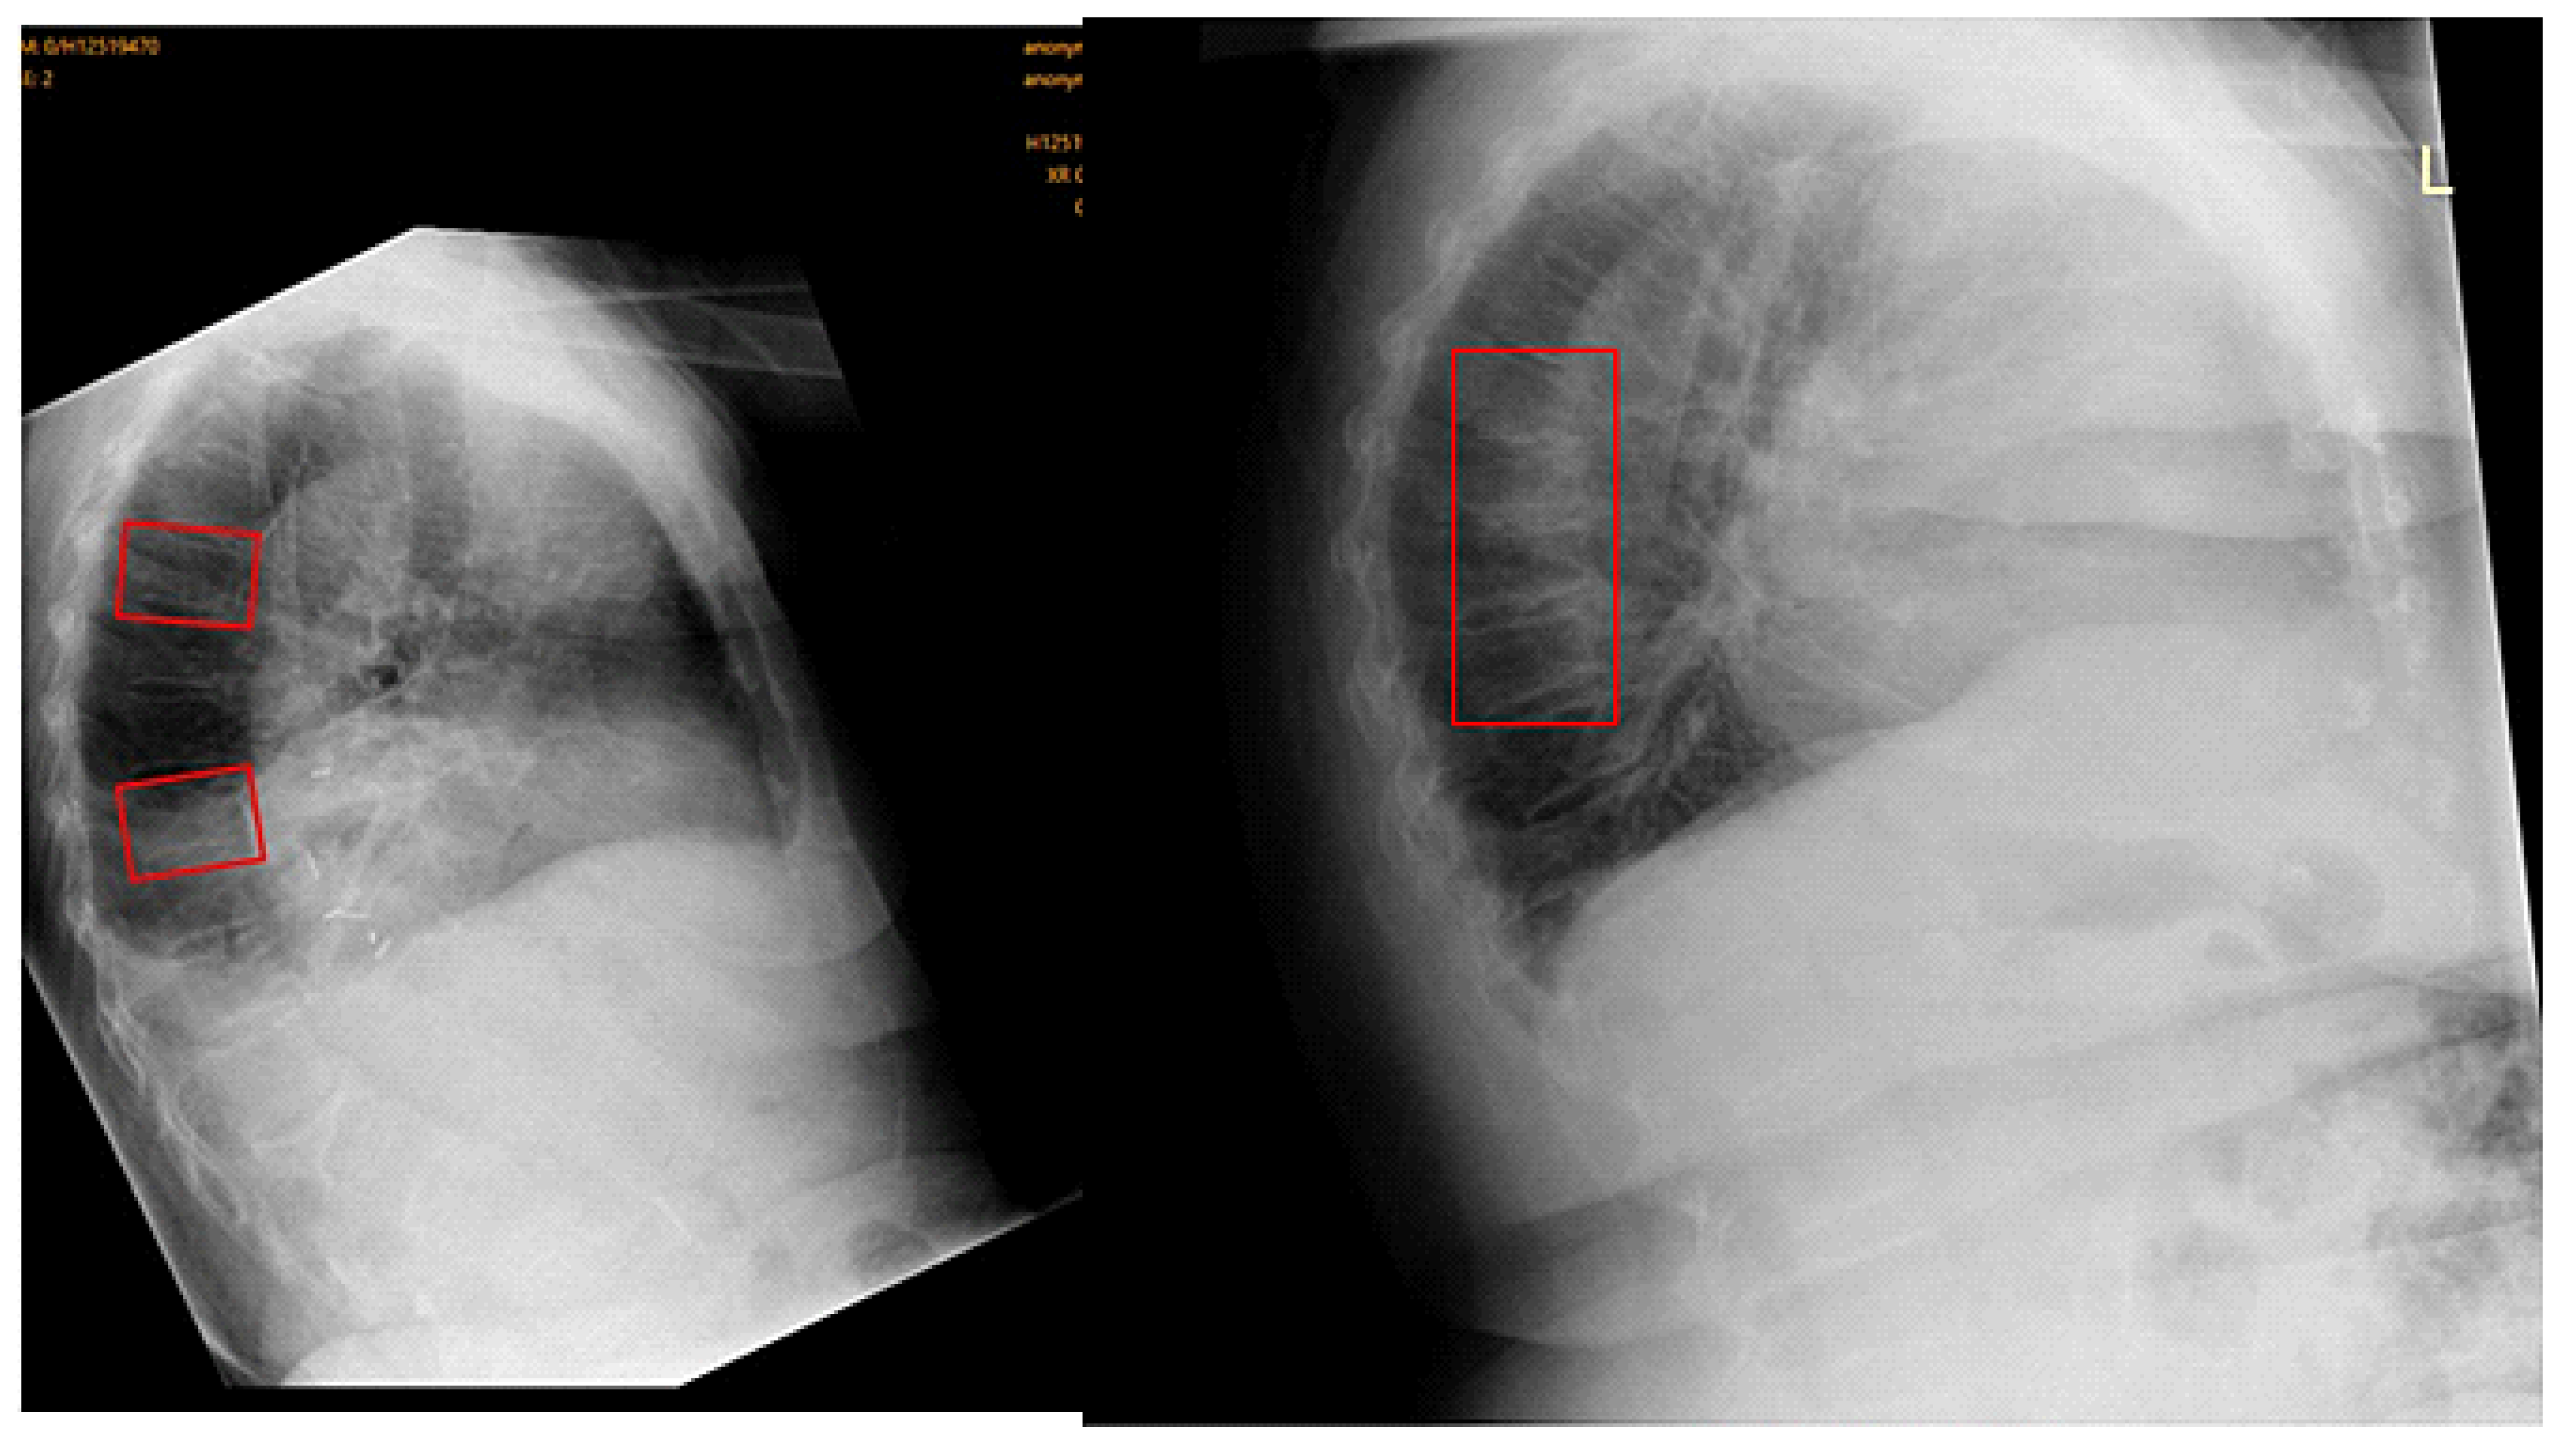

2.2. Image Analysis Using Ofeye 1.0 for Automatic Detection of OVFs

- Xiao, B.H.; Zhu, M.S.; Du, E.Z.; Liu, W.H.; Ma, J.B.; Huang, H.; Gong, J.S.; Diacinti, D.; Zhang, K.; Gao, B.; et al. A software program for automated compressive vertebral fracture detection on elderly women’s lateral chest radiograph: Ofeye 1.0. Quant. Imaging Med. Surg. 2022, 12, 4259–4271. [Google Scholar] [CrossRef]